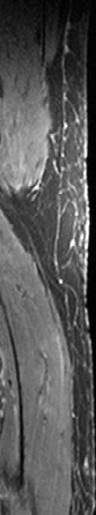

GanzkörperMR-Bildgebung mit koronarer Schnittbildebene. Die Erfassung der kompletten Körperlänge mit adäquater Weich teilauflösung ist ohne Einsatz ionisierender Strahlung möglich. Diese Technik wird in der onkologi schen, orthopä dischen und in der pädiatrischen Radiologie einge setzt.